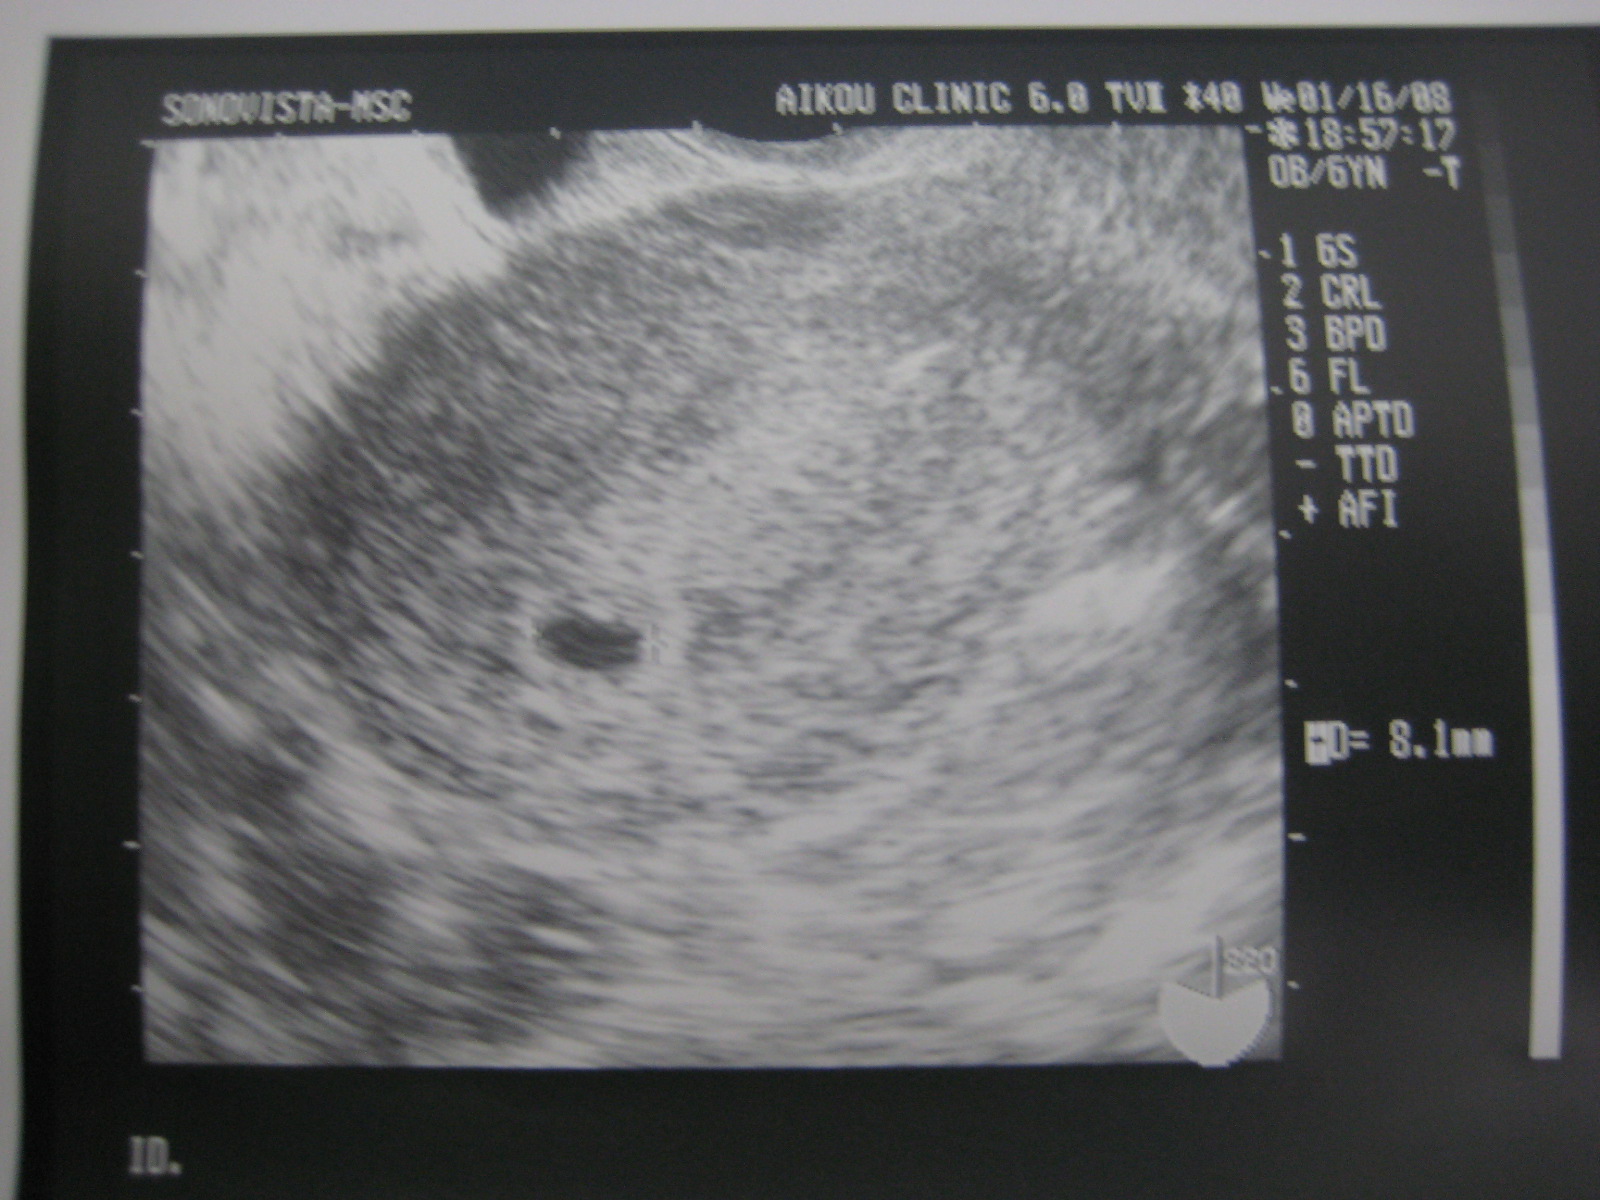

妊娠5週0日 5w0d の超音波 エコー 写真

妊娠5週0日 5w0d の超音波 エコー 写真

妊娠5週0日 5w0d の超音波 エコー 写真